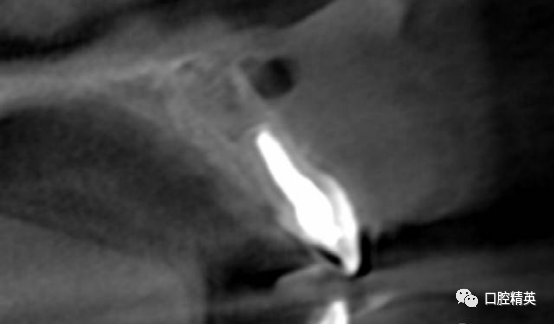

CBCT检查发现21内吸收,已做根充。根尖周可见约10mm*7mm*7mm范围低密度影像,近11,22根尖区。边界清楚。可见超充药物,查看病历曾使用碘仿和VITAPEX。

囊肿后壁与骨面粘连严重,术中破裂,可见大量豆渣样组织和药物颗粒。

初步清除。21根尖完全暴露。刮除21根尖区腭侧囊壁,此区域操作不便,易留有残留组织。